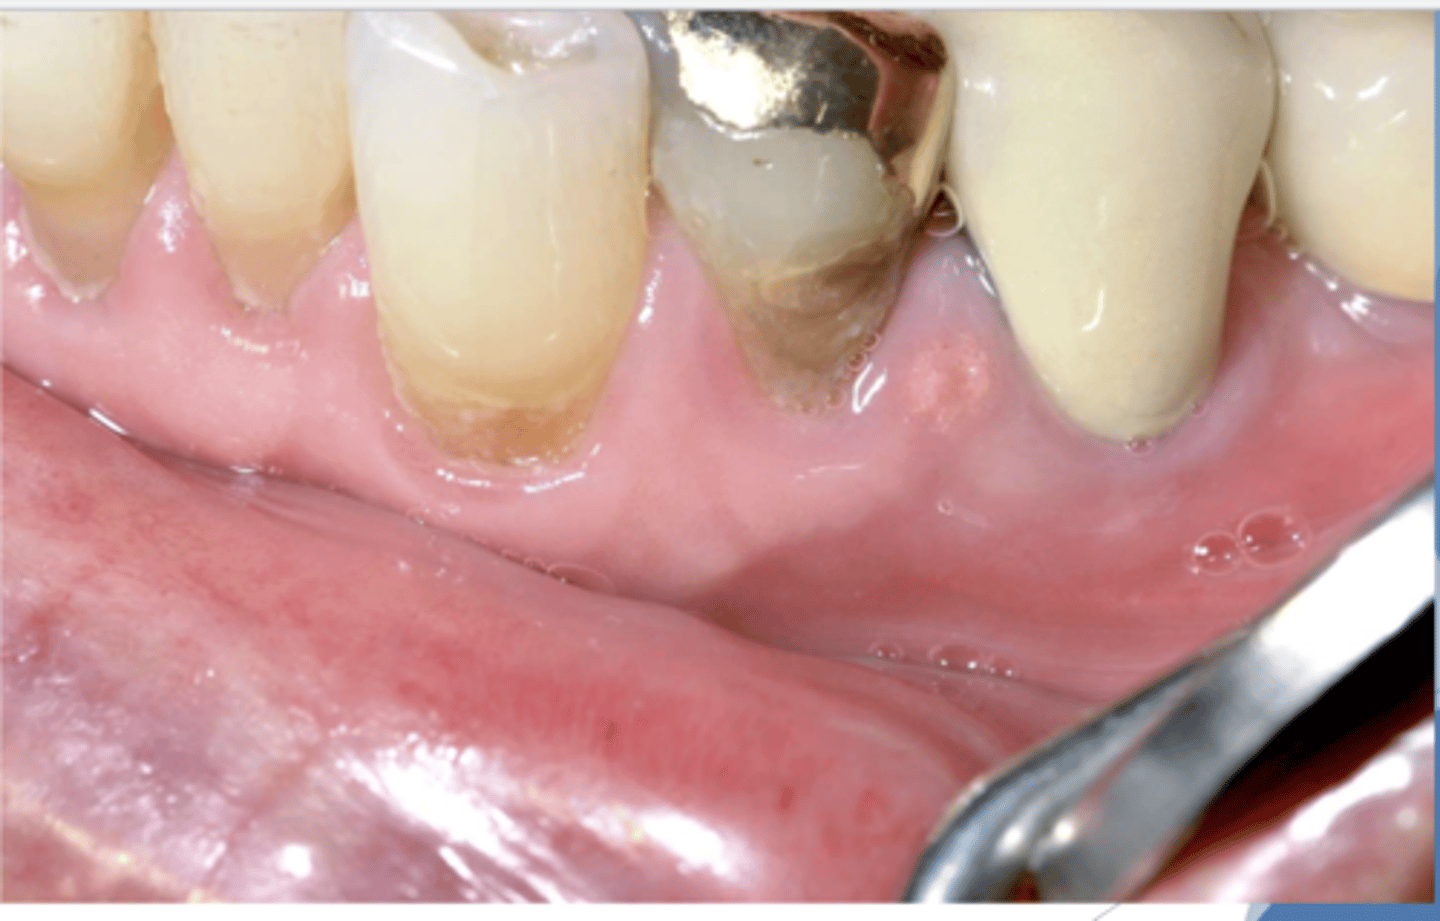

What do you suspect?

epulis fissuratum

What do the following clinical features describe?

-single or multiple folds of hyperplastic tissue in alveolar vestibule

-fibroepithelial poly/leaf-like denture fibroma may be seen along palatal mucosa